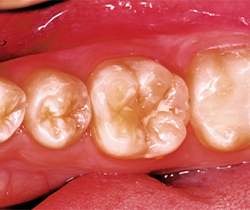

After occlusion is adjusted and restorations are finished and polished with OptraPol polishing cups and points (Ivoclar Vivadent), final radiographs and photos are taken to demonstrate the radiopacity of the material, the ideal interproximal contours and sealed margins, and its monolithic, void-free qualities (Figs. 16-20).

Fig. 18 Fig. 19

Class II restorations are cured for 10 seconds from the occlusal, then the ring and band are removed and the proximal surfaces are cured for an additional 10 seconds. Both the practitioner and the assistant have Bluephase Styles and this speeds up cure times by enabling multiple teeth curing at the same time as well as multiple surfaces.